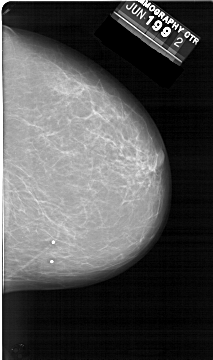

A_1398_1.LEFT_MLO

LEFT_MLO LINES 6871 PIXELS_PER_LINE 4186 BITS_PER_PIXEL 12 RESOLUTION 43.5 OVERLAY